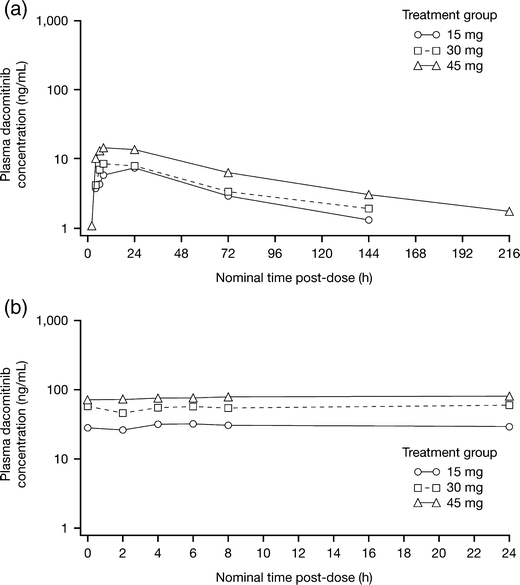

Mean plasma concentration–time profiles and PK parameters for dacomitinib following single (D-9) and multiple (C1D14) dosing are shown in Fig. 1 and Table 3.

Fig. 1

Mean (SD) plasma concentration–time profiles of dacomitinib following single (panel a; D-9) and multiple (panel b; C1D14) dosing

Following single oral dose administration (D-9), median Tmax ranged from 6 to 24 h over a dose range of 15–45 mg. The mean values for the PK parameters representing systemic exposure in rate (Cmax) and extent (AUCinf) increased along with dose in a proportional manner. Dose-proportionality was confirmed by consistency in the mean values for dose-normalized Cmax and AUCinf across the dose range studied. Mean apparent clearance ranged from 23.7 to 32 L/h across the 15–45 mg dose levels.

Mean Cmax and AUCτ increased after multiple dosing (C1D14). The geometric mean accumulation ratio ranged from 6.32 to 7.37 over the dose range. These calculated values are within an anticipated range based on the estimated half-life of dacomitinib and the daily dosing schedule. The linearity ratio was close to 1 across the studied dose levels. These reported parameters suggest that dacomitinib has linear kinetics after single- and multiple-dose administration in the dose range studied.